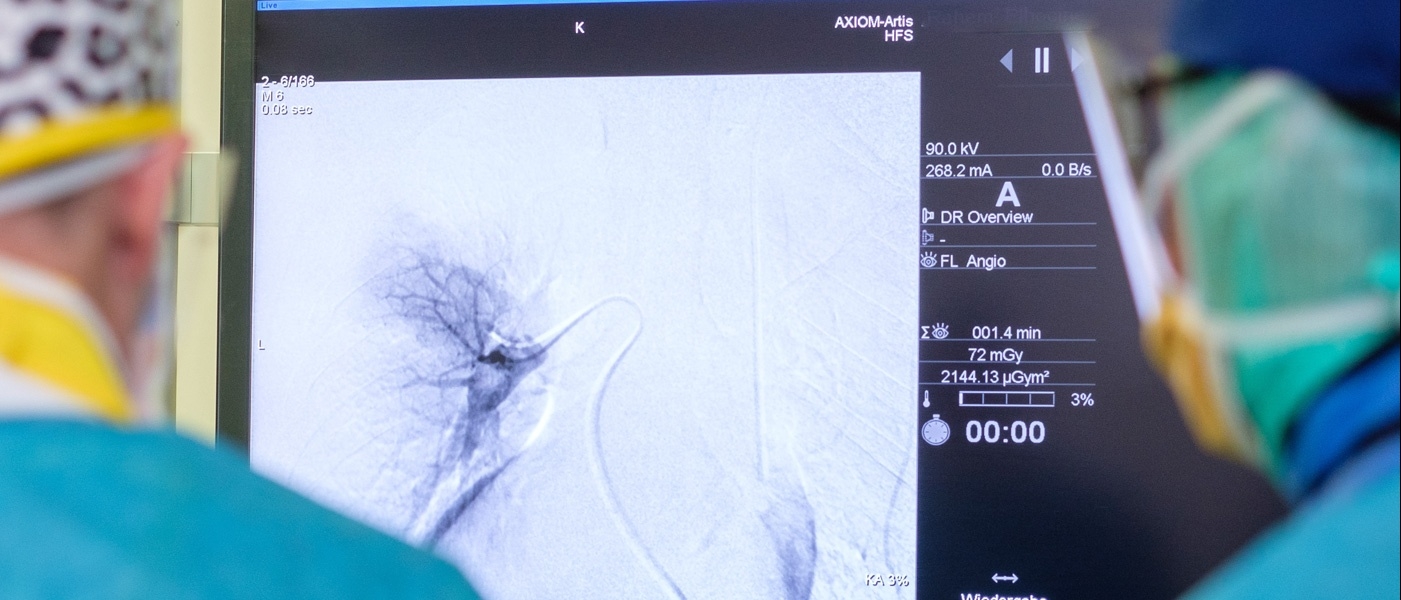

What modern technical equipment does the hospital include?

Among the leading technical equipment: are a gamma scalpel and a DaVinci robot. GammaKnife is an ultra-modern radiosurgical device that successfully treats tumors without open surgery. At the same time, DaVinci is designed to perform complex operations minimally-invasively.